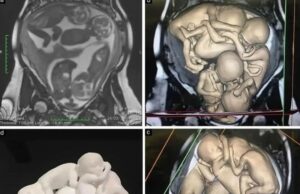

Seorang wanita berusia 32 tahun tanpa sebarang sejarah perubatan yang ketara telah dianugerahkan diagnosis endometrioma bilateral dan endometriosis peritoneal setelah mencuba untuk hamil selama...